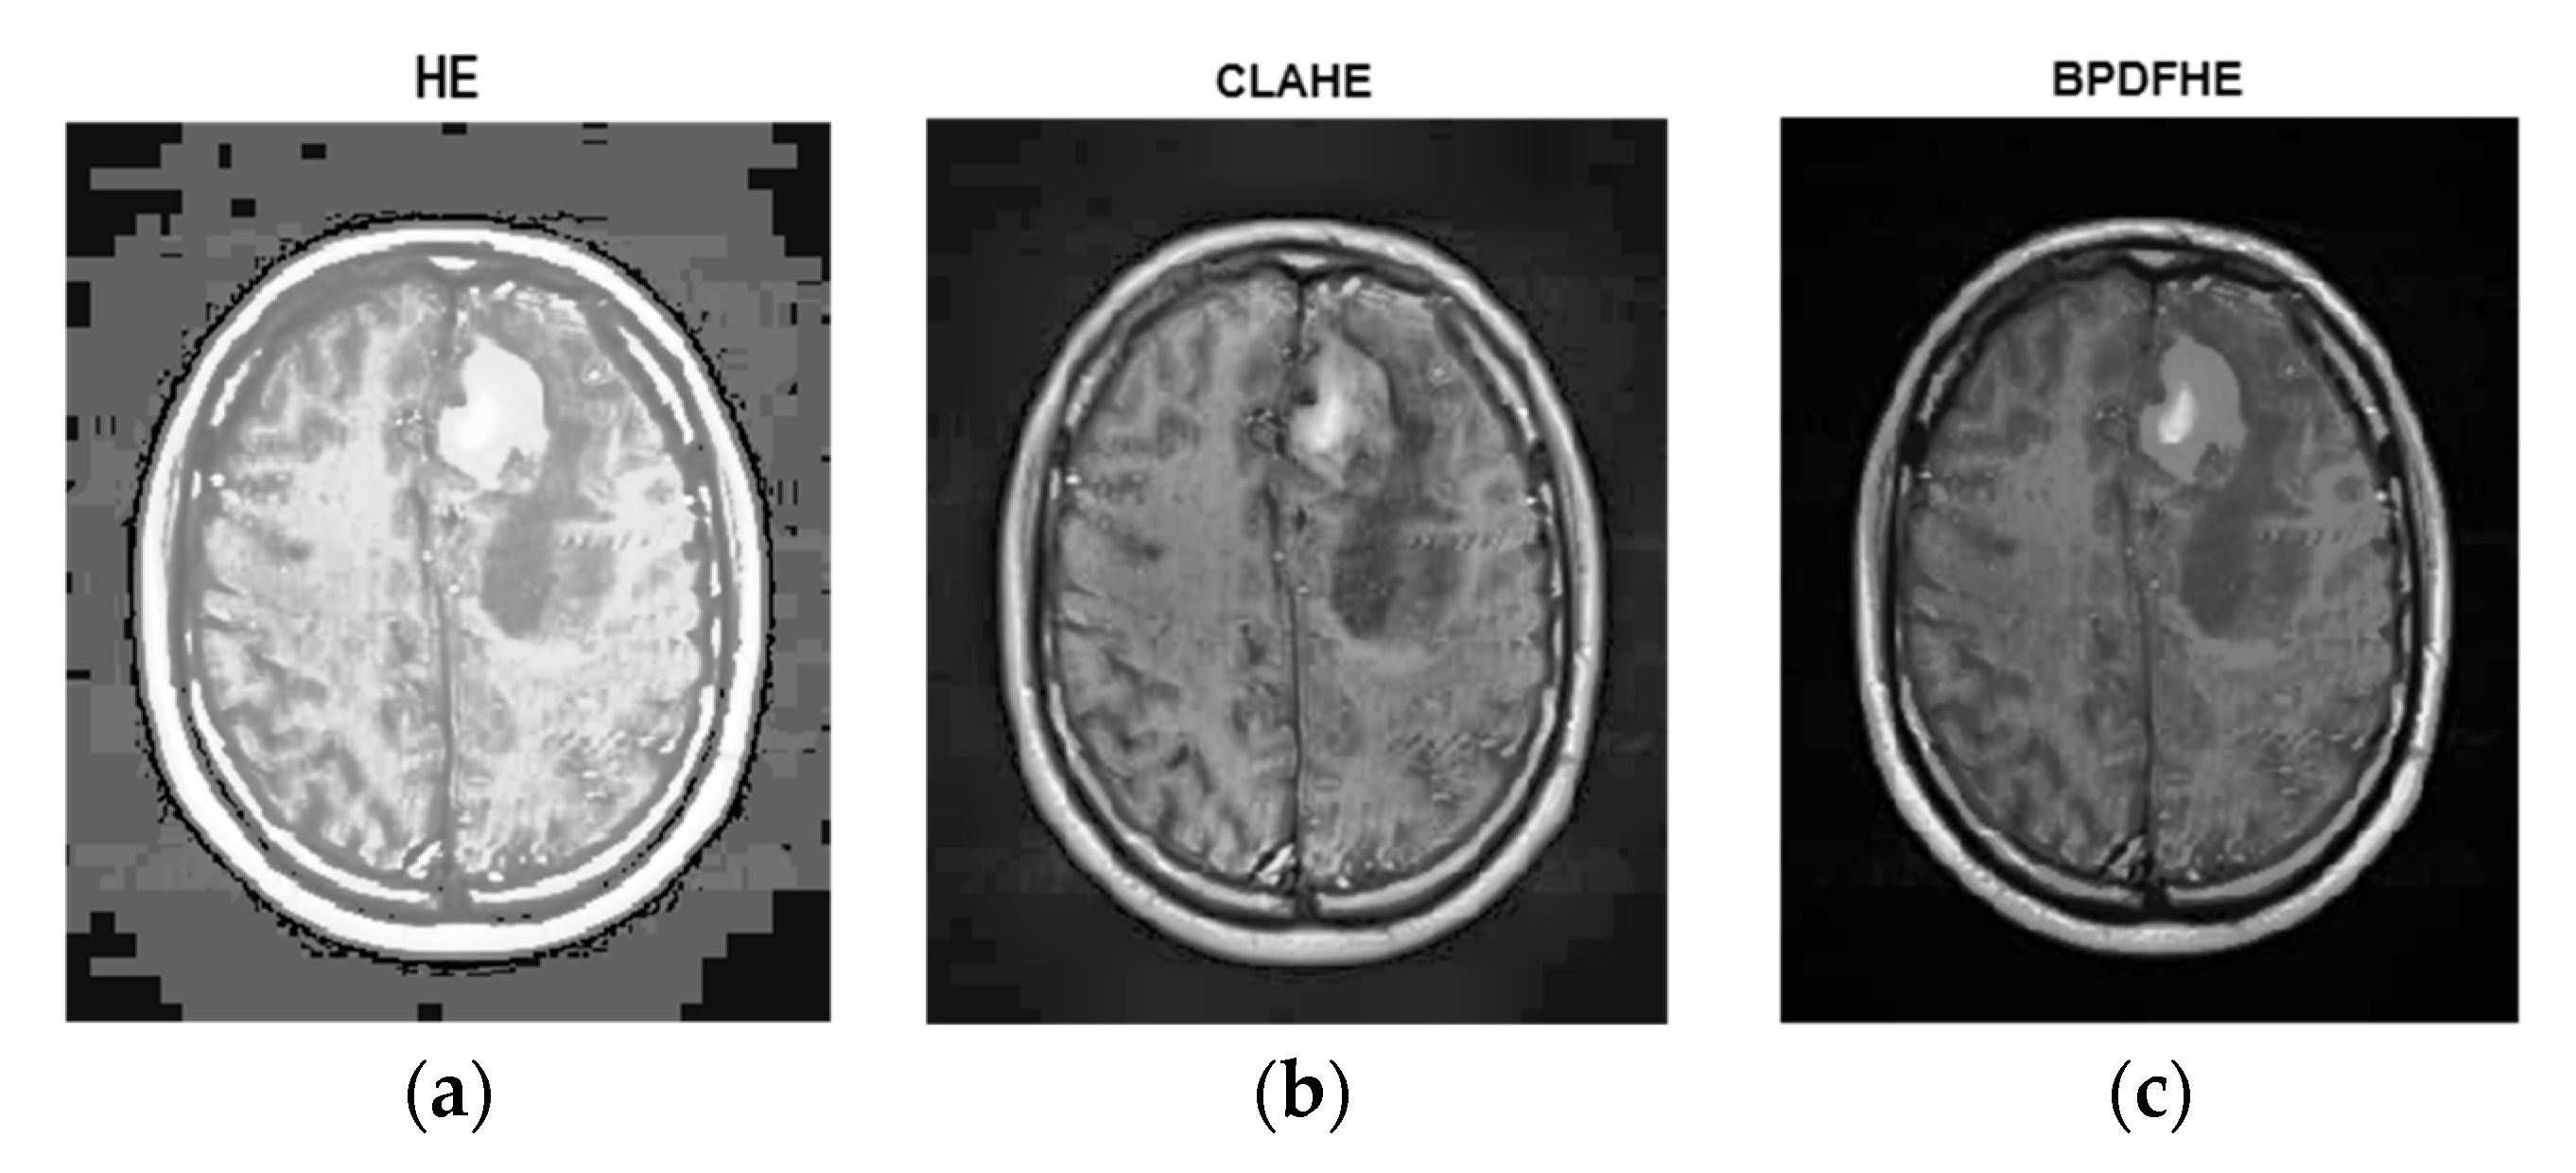

3.3. Segmentation Results: With vs. without Preprocessing

The upcoming figures are sectioned into three parts: Each part has an original neonatal brain image, and segmentation is achieved on that image. All the sections were subdivided into two parts—a and b. Part ‘a’ helps in visualizing tumor detection over the original image (which is not enhanced). On the other hand, part ‘b’ is of the enhanced image. Figure 10 represents the (a) original image, (b) preprocessed with BPDFHE enhanced image, (c) segmentation result using the median filter, (d) detection of the tumor, and (e) extraction of the tumor using thresholding.

The estimation of the proposed hybrid method for preprocessing and segmentation using a machine learning algorithm was shown on various MRI images to detect tumors. We placed the images for better visibility after simulations in ink space were used.

Justification of the results was carried out with the dice index (DI) and Jaccard index (JI). The ground truth (GT) image was considered to estimate the performance, which was prepared with the help of a radiologist.

The proposed ARKFCM technique considers spatial information of pixels for processing images which are affected by artifacts such as noise and intensity in-homogeneities. Hence, this procedure includes the effect of neighborhood pixels/voxels aimed at spatial information. Thus, it is capable of extracting boundaries in a proper way when compared to the existing, conventional FCM technique. It was witnessed that the implemented method was able to classify the effects of shielding and bright variations. Therefore, in brief, the main advantages of the proposed method were identified as robust to noise and shielding effects. The computable calculation was performed with Dice Index (DI) and Jaccard Index (JI) metrics [33], processing the difference between the segmented and GT images.

Segmentation results of the proposed method are shown in Figure 11 and Figure 12. The obtained numerical values are tabulated in Table 5 and Table 6 respectively, including the performance measures of dice similarity and Jaccard index. The proposed method provides efficient and robust results when compared to the FCM technique by a mean of a 98.86% dice index and 96.9% Jaccard index. This helps the physician to check whether the presence of any abnormalities is available in the MRIs corresponding to different parts of the brain. We conclude that the proposed remodified FCM technique ARKFCM method is more robust to noise and shading effects; the major advantage of using this technique is locating the tumor and affected regions.

Figure 12.

In the figures, the first image in the is the original image, the second image is the segmentation result of the first one, and the third image represents the extraction of the tumor succeeding segmentation. Similarly, in Figure 12, row 2 (b), the first figure is the preprocessed result of the original image, and the second and third images are same as above. From the third part, it is visualized with ease that the result of the tumor extraction does have more precision in the case of part ‘(b)’ compared to part ‘(a)’.